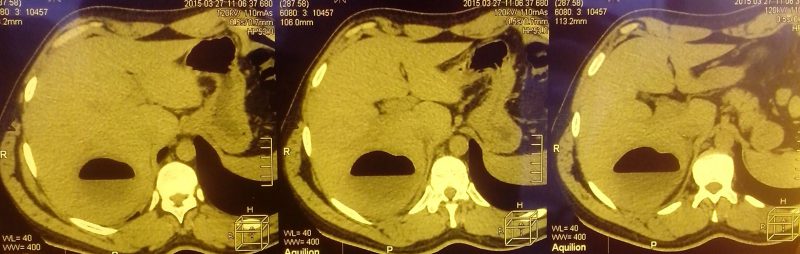

Чтобы диагностировать эту патологию пациентам придется пройти аппаратное обследование, в частности магниторезонансную и компьютерную томографию. В обязательном порядке они должны сдать ряд анализов, благодаря которым специалистам удастся выявить возбудителя, находящегося в вегетативной стадии, а также поглощенные эритроциты.